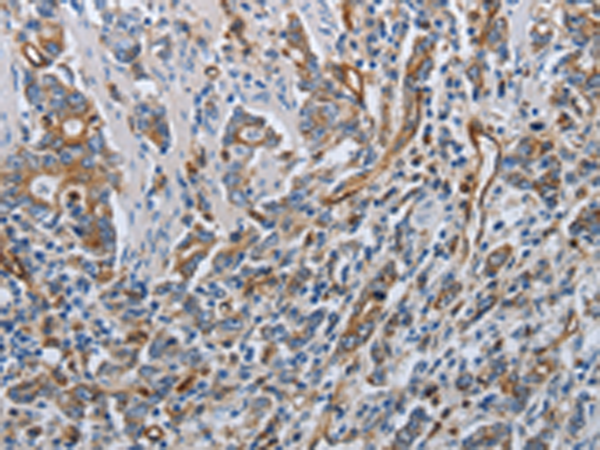

分类: 科研抗体货号: P04198别名: R16; AAAT; ATBO; M7V1; RDRC; ASCT2; M7VS1应用: IHC反应种属: Human